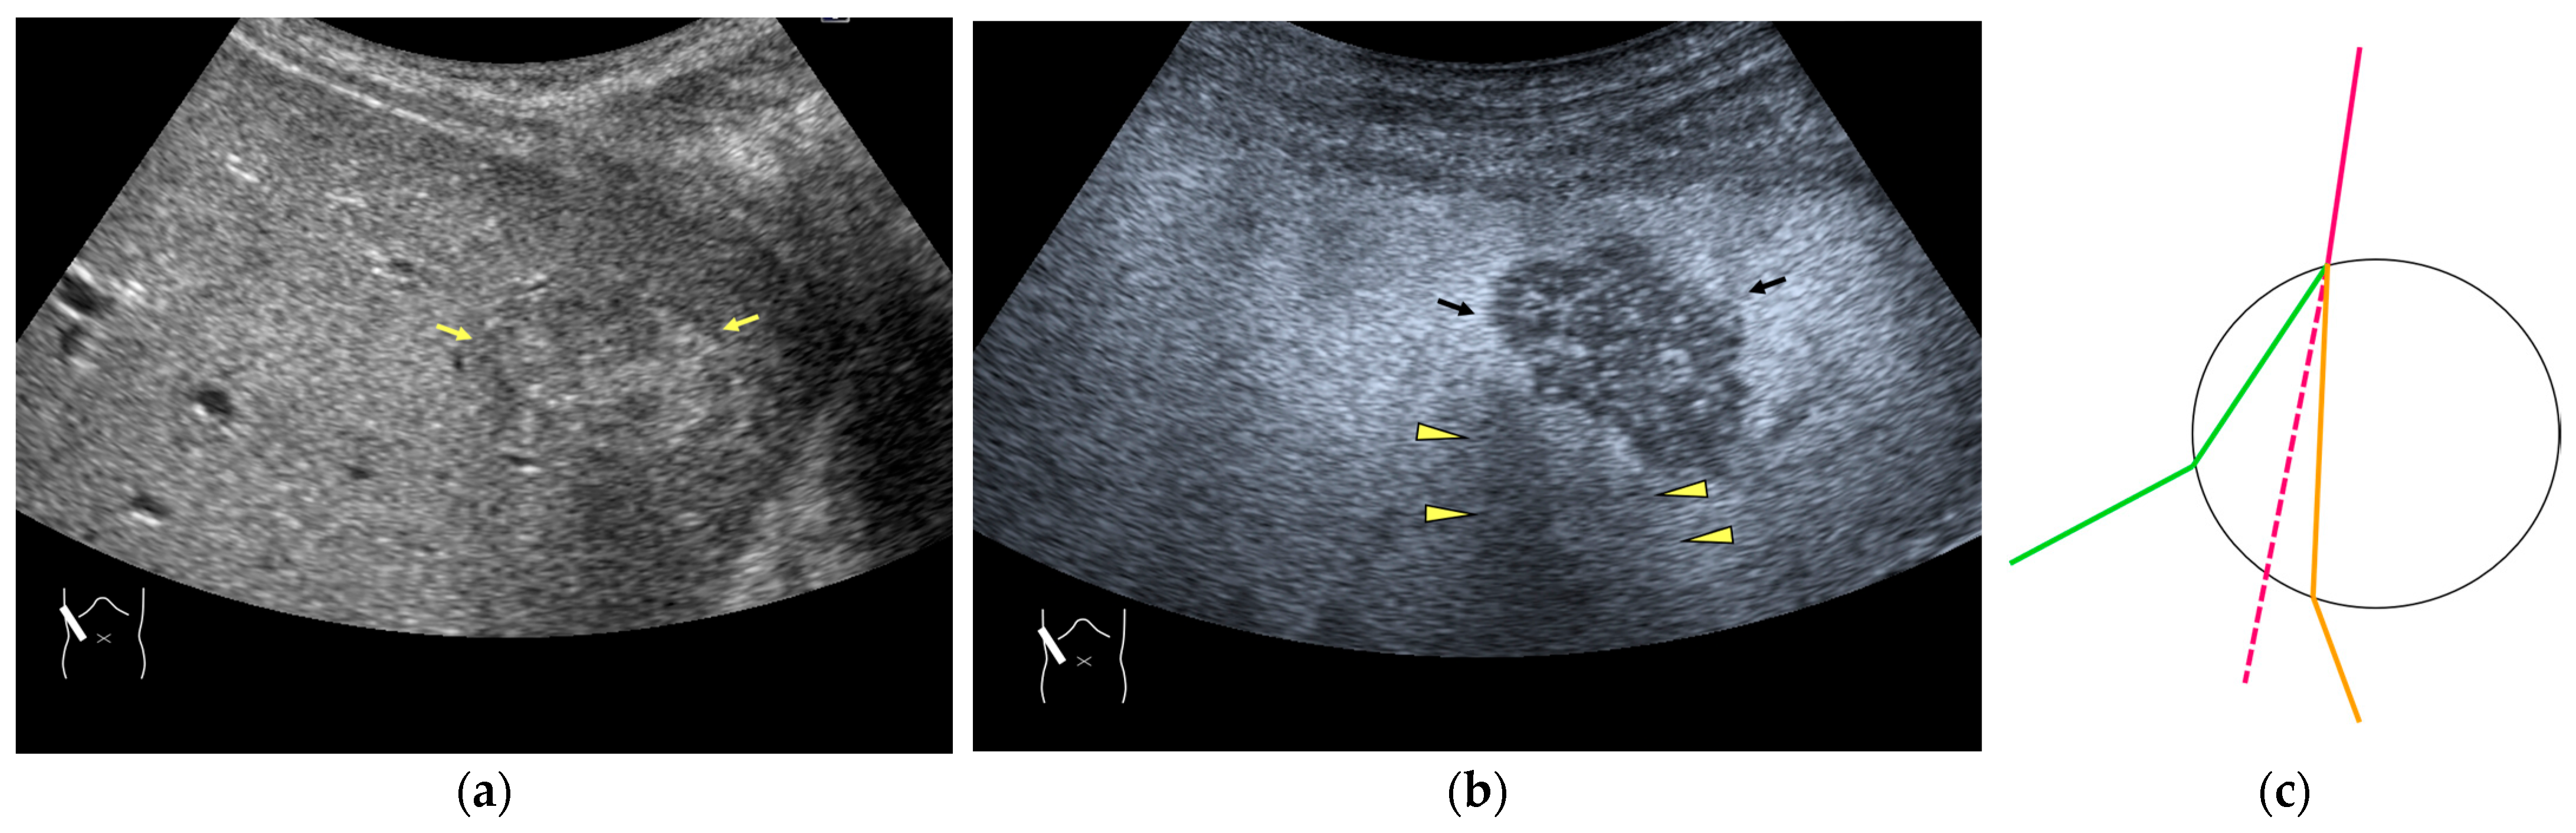

Figure 4.

Refraction artifact (2): heterogeneous enhancement behind a mass lesion (liver metastasis). (a) Gray-scale US shows a 5 × 4 cm liver mass (arrows) in the right lobe. (b) CEUS shows it to be enhanced (black arrows, mass lesion). The liver parenchyma behind it is also coarsely enhanced (arrowheads). (c) A schematic drawing of sound refraction through a round mass (black circle) shows that the US beam is refracted twice at the liver parenchyma–mass lesion interface. Non-refractive lines are marked with solid and dashed pink lines. When the acoustic velocity in the mass is less than that in surrounding tissue, it is indicated with an orange line. When it is greater than that in surrounding tissue, it is indicated with a green line.